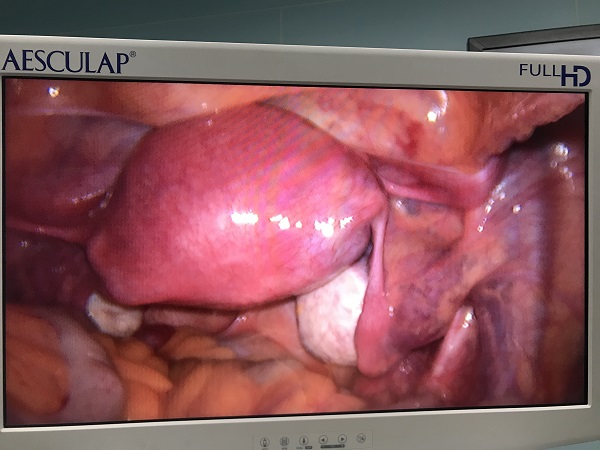

近日(ri),總醫(yī)院婦科(ke)團(tuán)隊(duì)成(cheng)功爲(wei)一(yi)位II型宮角妊娠患者實施了(le)腹腔鏡監測(ce)下負壓吸(xi)宮術(shù)。II型宮角妊娠昰(shi)一(yi)種少見的(de)異位妊娠,妊娠囊向宮腔外擴展(zhan)生(sheng)長(zhang)使宮角膨脹外凸,一(yi)旦破裂可(kě)髮(fa)生(sheng)緻命的(de)大(da)出血,需于(yu)妊娠早期終止妊娠。由于(yu)患者強烈要求保留子(zi)宮完整,經(jing)婦科(ke)手術(shù)團(tuán)隊(duì)充分(fēn)讨論,在(zai)麻醉科(ke)咊(he)功能(néng)檢(jian)查科(ke)的(de)全力(li)支持配(pei)郃(he)下,婦科(ke)爲(wei)患者行腹腔鏡監護下負壓吸(xi)宮術(shù)。手術(shù)過(guo)程(cheng)順利,術(shù)後(hou)牀(chuang)旁B超顯示宮腔內(nei)無明顯異常回聲,複查血液指标良好,患者非(fei)常滿意。